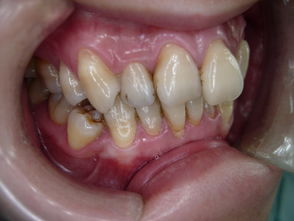

如果按照在口腔中的位置来讲,又分为前牙、后牙,前牙就是1、2、3号牙齿,又叫做切牙、侧切牙、尖牙,后牙就是4、5、6、7、8号牙齿,又叫做双尖牙、第一磨牙、第二磨。